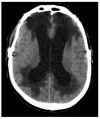

Cerebral edema is the abnormal accumulation of fluid in any of the tissue compartments of the cerebral parenchyma. It remains a significant challenge in neurotrauma care because it contributes to secondary brain injury, affecting prognosis. This review analyzes the recent literature, including foundational studies, to describe the mechanisms of distinct types of cerebral edema following traumatic brain injury (TBI). Emerging concepts, such as the role of the glymphatic system and heme-derived inflammasomes, offer new insights into new types of edemas, differentiated by pathogenesis and potential treatments. Recent advancements in understanding these molecular mechanisms can improve therapeutic strategies, facilitating a better approach in the era of precision and personalized medicine. Although there has been notable progress, a proposal to customize treatments for diverse types of edemas is necessary to improve outcomes following traumatic brain injury. In this review, we describe the current subtypes of post-traumatic brain edemas and link them to a specific management approach.